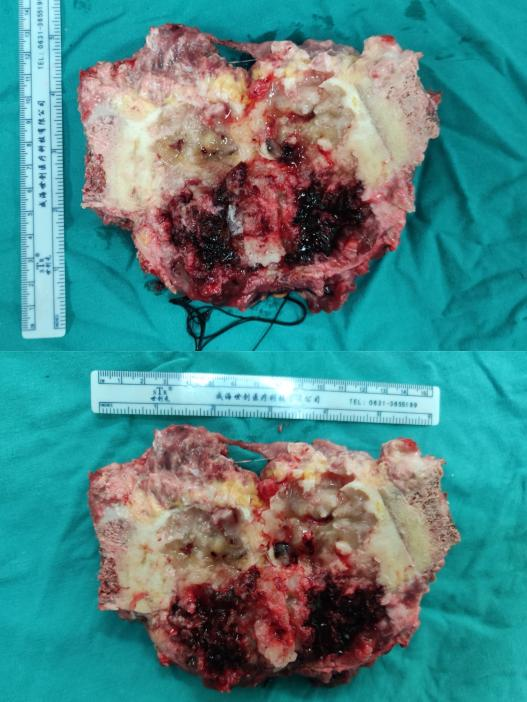

(如图所示三者高度吻合,手术按计划完成)

通过术前规划手术路径及肿瘤切除范围,以及重要部位的精准参数,西安市红会医院骨病肿瘤科为患者制定了个体化治疗方案,杨团民主任医师主刀顺利实施了“右侧坐骨软骨肉瘤瘤体切除、血管、神经探查、髋臼周围重建术”,肿瘤完整切除,体积约9cmx8cmx6cm。剖开标本显示肿瘤浸润边界距离正常髋臼侧骨组织1cm,肿瘤边界切除精准。